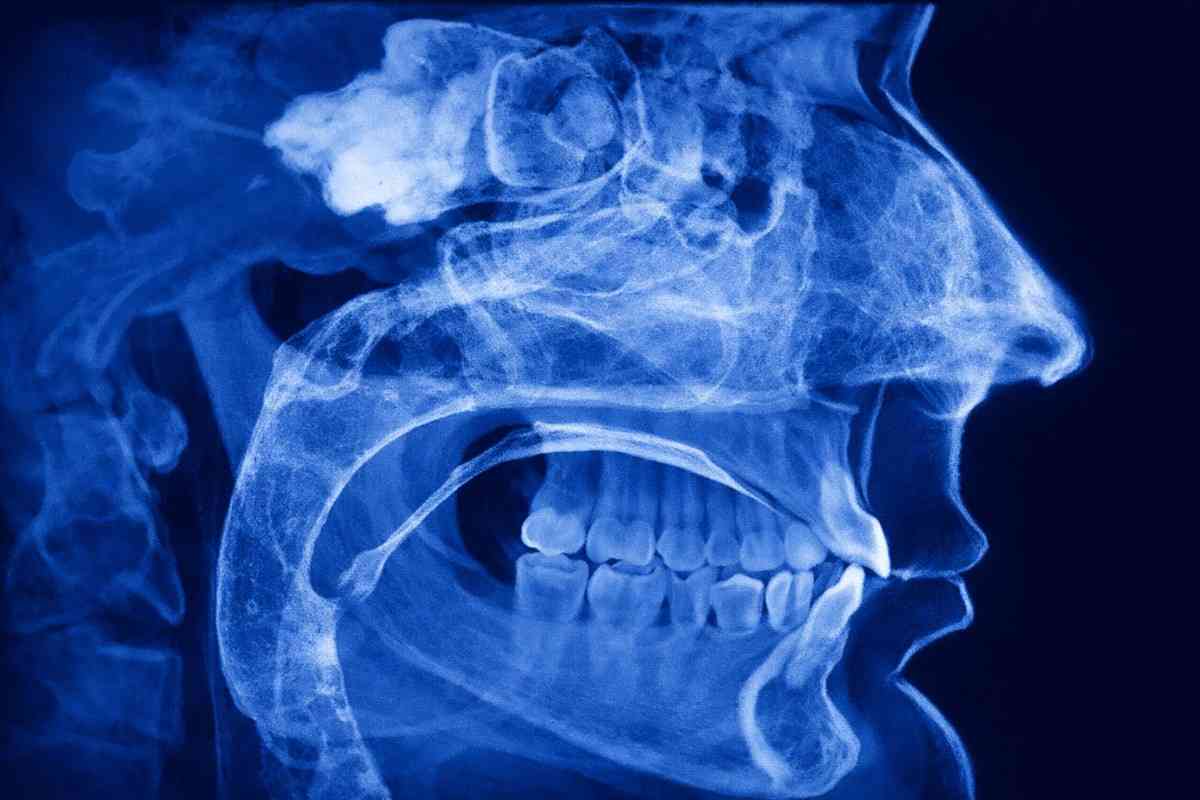

VELMENI for Dentists® 3D

Create 3D realizations of 3D/CBCT scans in minutes. Reveal nerves, sinuses, TMJ, airways, and important anatomical features for medical detections, treatment planning, and patient education.